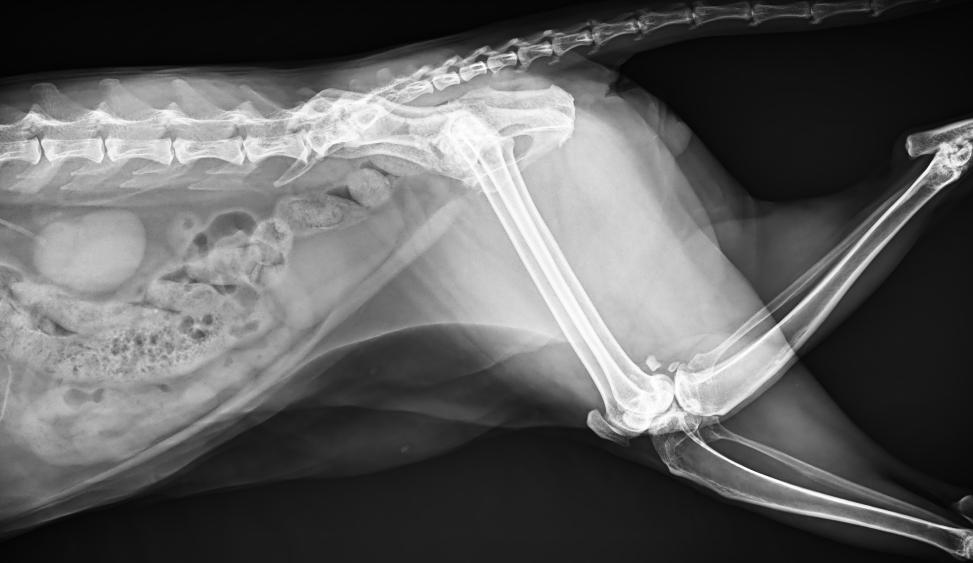

● 17*17大尺寸平板探測器,獲得高質量圖像

● 優(yōu)異的空間分辨率及信噪比,提升圖像質量

● 采用線噪聲消除技術,使成像質量提升40%

● 進口高品質球管,大功率、高熱容量、微焦點,1.0/2.0mm雙焦點設計

● 25kHz高主逆變頻率,輸出電壓更穩(wěn)定;瞬時定格影像,無拖尾現象

● 智能高效的圖像處理軟件,大幅提升圖像質量